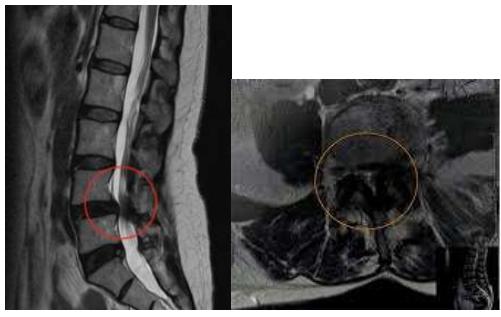

CASO CLÍNICO.

Paciente de 68 anos, sexo masculino, veio encaminhado do município de São Bento do Una-PE para parecer com

a neurocirurgia. Tinha relato de lombalgia, claudicação, dor, dormência e fraqueza em membros inferiores

progressivas, além de incontinência urinária há 6 meses. Negou diabetes, hipertensão e dislipidemia. É vendedor

ambulante de leite, faz uso de bicicleta no trabalho e relatou queda da mesma 3 dias antes do surgimento dos

sintomas, sem perda de consciência e sem vômitos. Ao exame físico: pulsos femoral, poplíteo, pedioso e tibial

posterior presentes bilateralmente, sem alterações de pele em membros inferiores, sinal de Lasègue negativo

bilateralmente, teste de Kemp com dor e formigamento durante sua execução em membros inferiores, além de

alterações motoras e sensitivas correspondentes às raízes nervosas de L4, L5 e S1.

Foi internado em enfermaria da Neurocirurgia, fez tomografia computadorizada (TC) de crânio que foi normal

para a idade, TC e ressonância magnética (RM) de toda coluna que mostrou estenose importante de canal

vertebral na altura de L4, algumas alterações degenerativas discretas no restante da coluna, incluindo a cervical

e sem sinais de fratura vertebral.